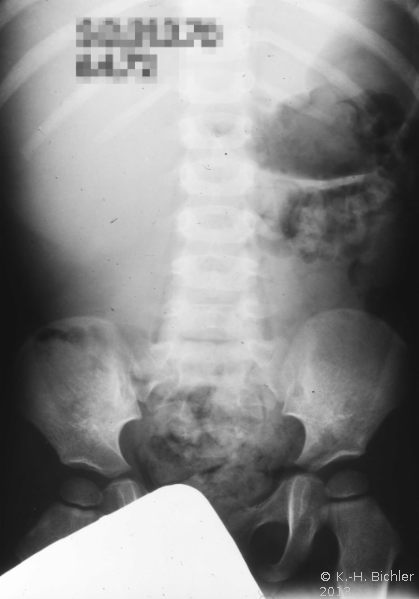

Die abdominale Sonographie bzw. die Computertomographie haben die Ausscheidungsurographie als die bildgebende Untersuchungstechnik bei Patienten mit Oberbauchtumor, z.B. Wilmstumor, verdrängt. Einige Ausscheidungsurographien von Kindern mit Wilmstumoren aus unserer Sammlung aus den 70er Jahren des vergangenen Jahrhunderts sind aus didaktischen Gründen hier wiedergegeben. Die Bilder zeigen instruktiv die Größe und Verdrängung durch den Tumor (

4 Abbildungen HG1).